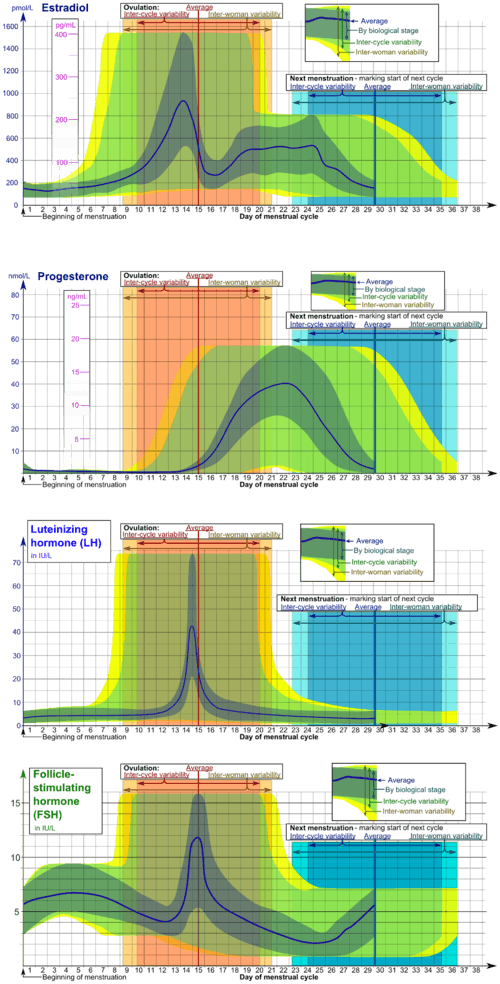

In humans, ovulation occurs about midway through the menstrual cycle, after the follicular phase. The few days surrounding ovulation (from approximately days 10 to 18 of a 28-day cycle), constitute the most fertile phase.[3][4][5][6] The time from the beginning of the last menstrual period (LMP) until ovulation is, on average, 14.6[7] days, but with substantial variation between females and between cycles in any single female, with an overall 95% prediction interval of 8.2 to 20.5[7] days.

The process of ovulation is controlled by the hypothalamus of the brain and through the release of hormones secreted in the anterior lobe of the pituitary gland, luteinizing hormone (LH) and follicle-stimulating hormone (FSH).[8] In the pre-ovulatory phase of the menstrual cycle, the ovarian follicle will undergo a series of transformations called cumulus expansion, which is stimulated by FSH. After this is done, a hole called the stigma will form in the follicle, and the secondary oocyte will leave the follicle through this hole. Ovulation is triggered by a spike in the amount of FSH and LH released from the pituitary gland. During the luteal (post-ovulatory) phase, the secondary oocyte will travel through the fallopian tubes toward the uterus. If fertilized by a sperm, the fertilized secondary oocyte or ovum may implant there 6–12 days later.[9]

Estrogen levels peak towards the end of the follicular phase. This causes a surge in levels of luteinizing hormone (LH) and follicle-stimulating hormone (FSH). This lasts from 24 to 36 hours, and results in the rupture of the ovarian follicles, causing the oocyte to be released from the ovary via the oviduct.[12]

The follicle proper has met the end of its lifespan. Without the oocyte, the follicle folds inward on itself, transforming into the corpus luteum (pl. corpora lutea), a steroidogenic cluster of cells that produces estrogen and progesterone. These hormones induce the endometrial glands to begin production of the proliferative endometrium and later into secretory endometrium, the site of embryonic growth if implantation occurs. The action of progesterone increases basal body temperature by one-quarter to one-half degree Celsius (one-half to one degree Fahrenheit). The corpus luteum continues this paracrine action for the remainder of the menstrual cycle, maintaining the endometrium, before disintegrating into scar tissue during menses.[14]

Females near ovulation experience changes in the cervix, in mucus produced by the cervix, and in their basal body temperature. Furthermore, many females experience secondary fertility signs including Mittelschmerz (pain associated with ovulation) and a heightened sense of smell, and can sense the precise moment of ovulation.[15][16]

Symptoms related to the onset of ovulation, the moment of ovulation and the body's process of beginning and ending the menstrual cycle vary in intensity with each female but are fundamentally the same. The charting of such symptoms — primarily basal body temperature, Mittelschmerz and cervical position — is referred to as the sympto-thermal method of fertility awareness, which allow auto-diagnosis by a female of her state of ovulation. Once training has been given by a suitable authority, fertility charts can be completed on a cycle-by-cycle basis to show ovulation. This gives the possibility of using the data to predict fertility for natural contraception and pregnancy planning.

Estradiol and progesterone, taken in various forms including combined oral contraceptive pills, mimics the hormonal levels of the menstrual cycle and engage in negative feedback of folliculogenesis and ovulation.